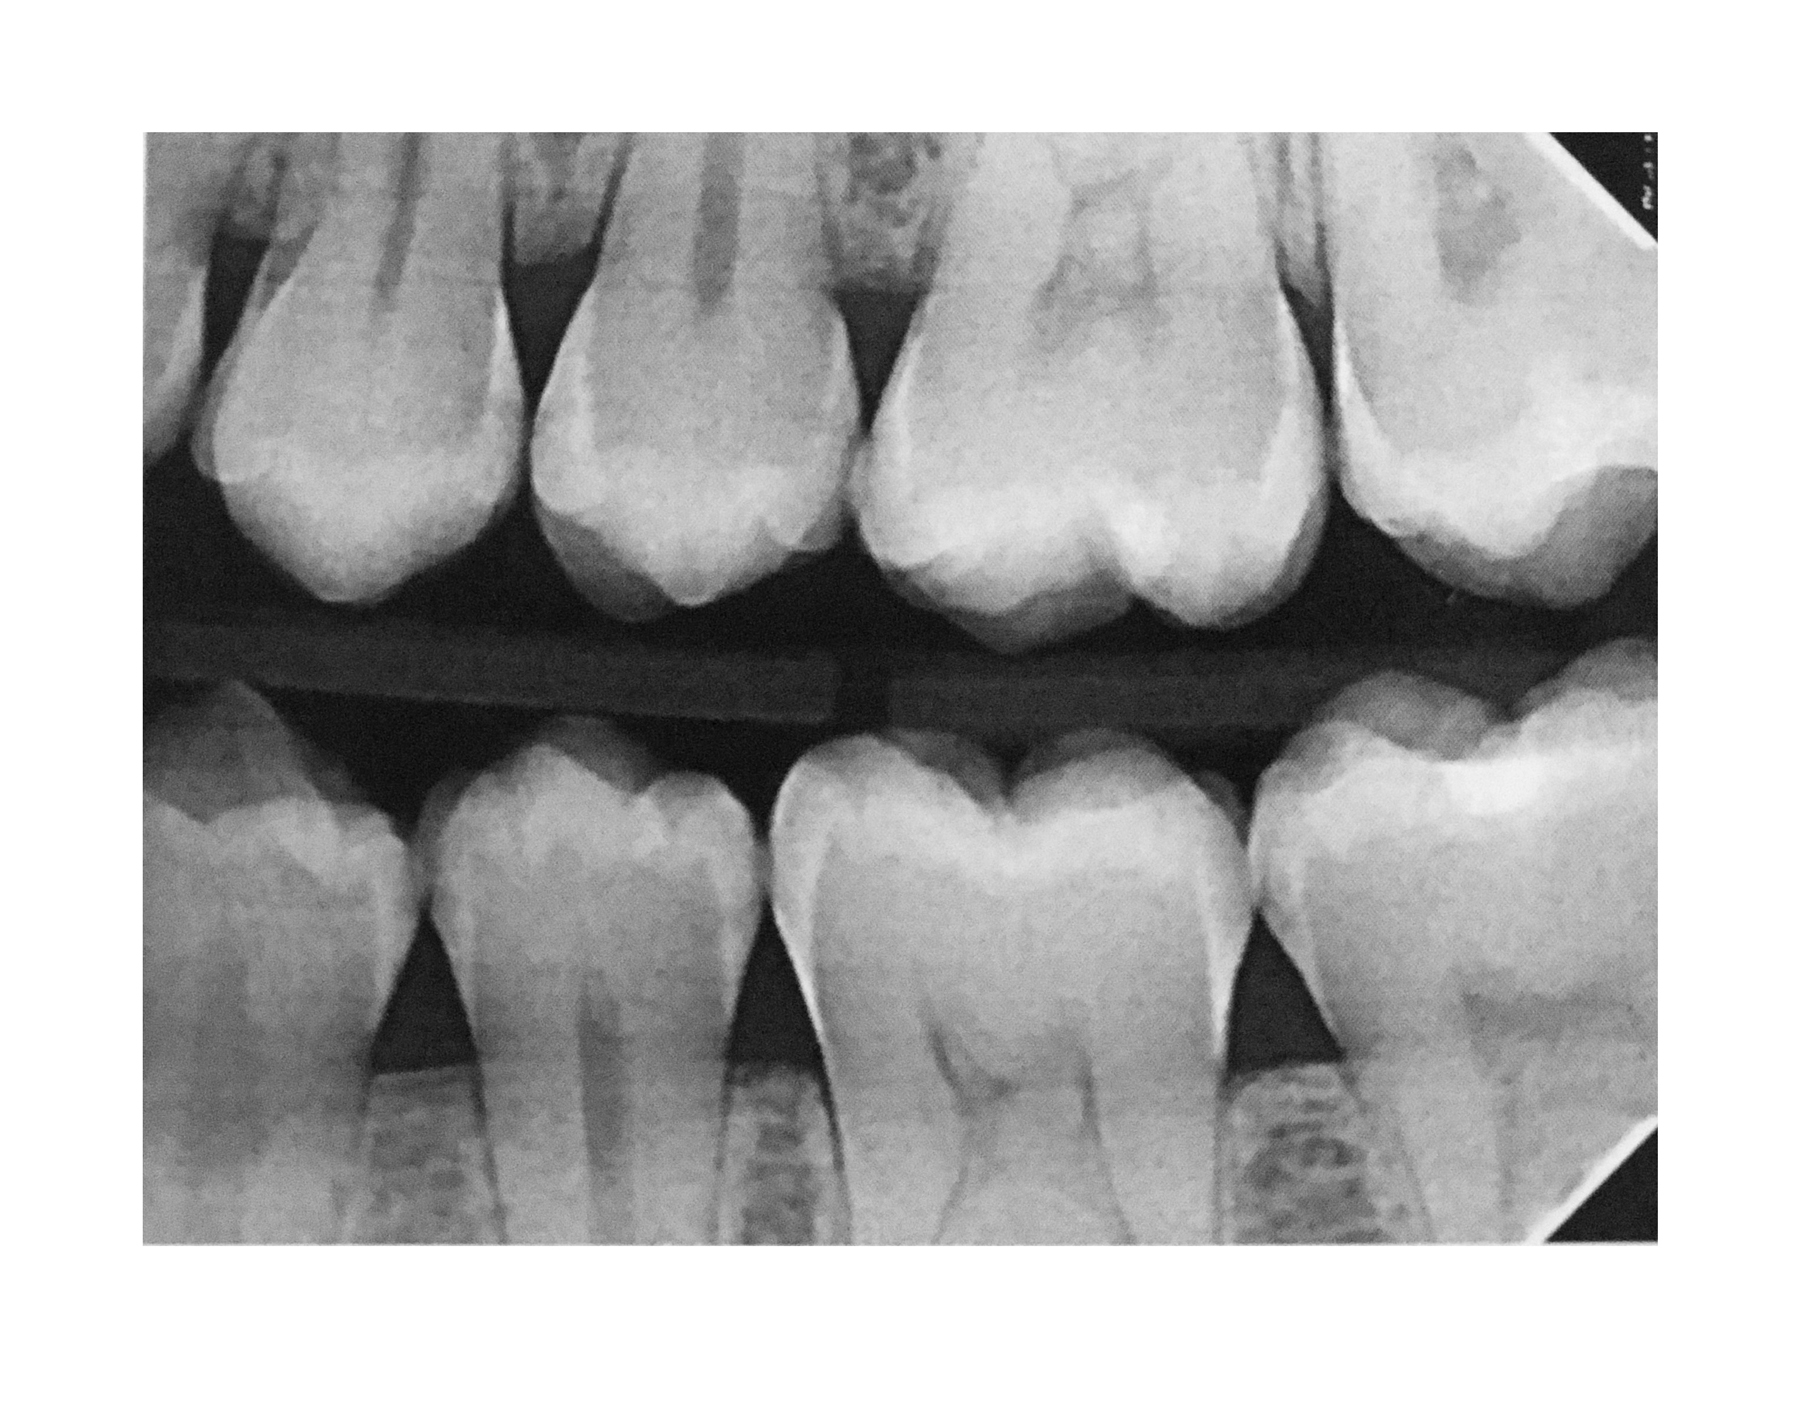

(18.) Radiograph of teenage patient showing maxillary left first premolar, which will be scheduled for disto-occlusal restoration, and all other proximal sites that will be treated with dental pick applied SDF. Additional application of SDF planned for 3 months and new bitewing films to be recorded in 6 months.

Figure 18